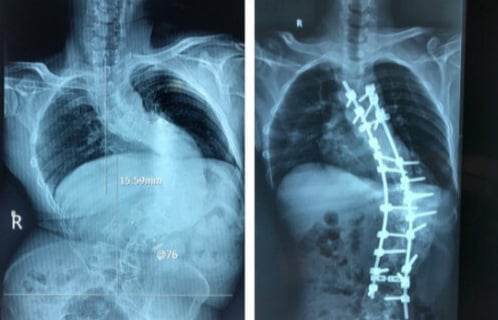

Bệnh viện Trung ương quân đội 108 vừa phẫu thuật thành công cột sống biến dạng cho nam bệnh nhân 44 tuổi ở Bắc Ninh.